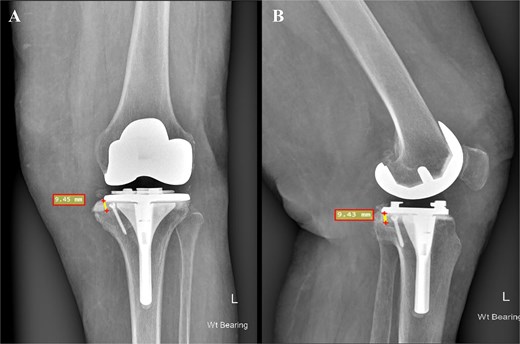

Intraoperatively, around 9-10 mm was noted between the medial plateau rim and the trial tibial implant, classifying the defect as Anderson Orthopedic Research Institute (AORI) Classification type IIA. Consequently, the bone cement with screw augmentation (BCSA) technique [10] was selected to address the defect and reinforce the medial plateau. Multiple drill holes were created within the defect area using a 2.7 mm drill bit. A single 3.5 mm stainless steel cancellous screw was inserted to provide mechanical support (Fig. 3). PMMA bone cement was then injected into the drill holes and the entire defect area. Excess cement was removed after the tibial component was firmly seated in place.

An intraoperative photograph showing the tibia after cuts made with customized 3D-printed guides. The non-contained 9.45 mm tibial bone defect was treated using the BCSA technique. Mechanical stability was ensured by the insertion of a 3.5 mm stainless steel cancellous screw.

In the present case, the BCSA technique was selected as the most suitable based on the pre-operative plan. The rationale for deeming BCSA the most appropriate option among others included the following: (i) the defect did not exceed 15%–20% of the tibial surface area, (ii) the technique permitted the use of standard primary TKA systems rather than necessitating revision prostheses as with metal augments, (iii) this method would preserve existing bone and soft tissue attachments, thereby facilitating both the planned primary and even a potential revision procedure, and (iv) the patient was obese with a BMI exceeding 30 and a diagnosis of established osteoporosis. Consequently, the use of excessive hardware combined with additional metal augments would elevate the mechanical load and increase the risk of future periprosthetic fracture. Our patient exhibited a bone defect of ~9.45 mm following the final tibial cuts (Fig. 3). Using cement alone in such a defect could have resulted in cement lamination, shrinkage, cracking, and early mechanical failure [17]. In our view, the application of the BCSA technique in this patient allowed for optimal cement pressurization within the defect, enhancing implant stability and fixation. At the 2-year follow-up, the patient showed excellent radiographic results (Fig. 4) and satisfactory clinical recovery (Video 1).

Postoperative face (A) and profile (B) X-rays depicting a medial tibial bone defect ~9.45 mm from the baseplate. The 3.5 mm cancellous screw is indicative of the applied BCSA technique.